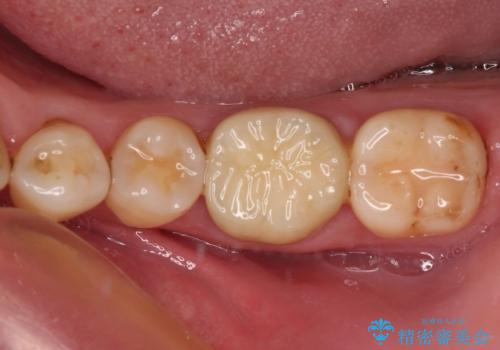

フルジルコニアクラウンは、やや光沢のある材質ですが、奥歯に装着した場合にはさほど気にならず、自然な口元の印象となりました。